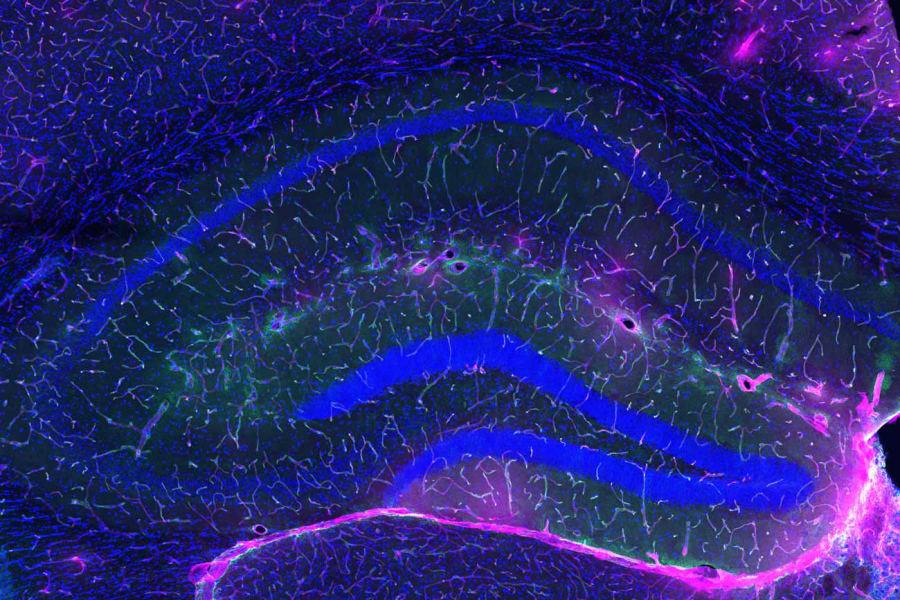

Imagen de portada